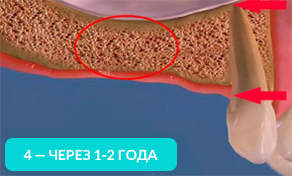

- Чем дольше Вы ходите хотя бы без одного зуба, тем больше убывает костная ткань. В 2-ух словах, для Вас это значит, что в будущем при отсутствии нескольких зубов, Вам необходимо будет либо делать дорогостоящее наращивание костной ткани, либо ставить съемные протезы (многие пациенты не соглашаются на этот вариант, но в силу дороговизны варианта с наращиванием костной ткани, им приходится ставить съемные протезы)

На 4-ом рисунке видно, что костная ткань стала значительно тоньше, теперь в это место уже невозможно установить импланты (потребуется операция по наращиванию костной ткани).

Обратите внимание, насколько тоньше стала кость на рисунке 4, как постепенно обнажается корень оставшегося зуба.

Убыль костной ткани распространяется на соседние зубы и их корни постепенно обнажаются!

Зубы, расположенные рядом с местом удаления, со временем становятся нестабильными и могут быть утрачены.